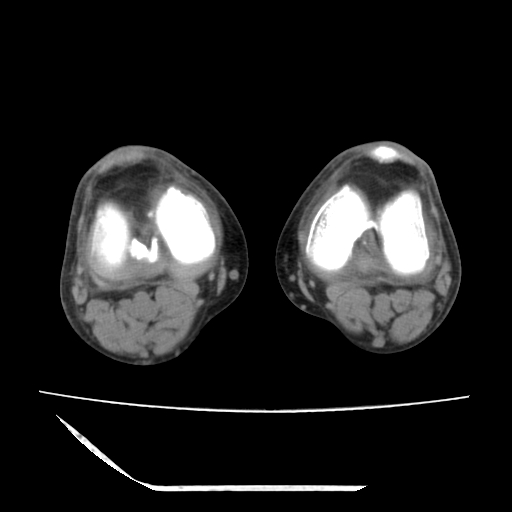

标题: CT13225:老年男性,左膝关节疼痛数月;请各位老师讨论。 [打印本页]

标题: CT13225:老年男性,左膝关节疼痛数月;请各位老师讨论。

骨质增生,骨性关节面硬化,关节积液,考虑退行性骨关节病

关节腔内少量积液,关节面退变。

双膝退变

骨质增生,骨性关节面硬化,关节间隙失常,关节积液,考虑退行性骨关节病.

骨质增生,骨性关节面硬化,关节积液,考虑退行性骨关节病。

这个病例诊断:退行性骨关节炎